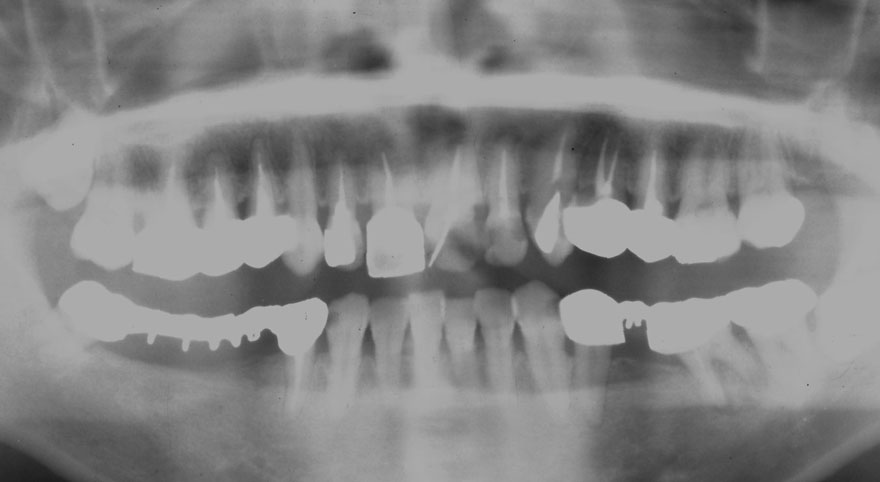

初診時 41歳 男性 平均歯槽骨喪失量:4.11mm

30年後 71歳

平均歯槽骨喪失量:3.70mm

30年間再生量:+0.41mm

年間再生速度:+0.014mm

(ケア頻度:1.27ヵ月ごと)